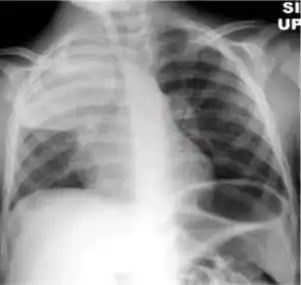

4. Pleural effusion - Presence of a significant amount of fluid within the pleural space. This finding must be distinguished from blunting of the costophrenic angle, which may or may not represent a small amount of fluid within the pleural space (except in children when even minor blunting must be considered a finding that can suggest active TB).

Chest x-ray showing dense opacity pleural effusion in the lower left lung of primary pulmonary TB.